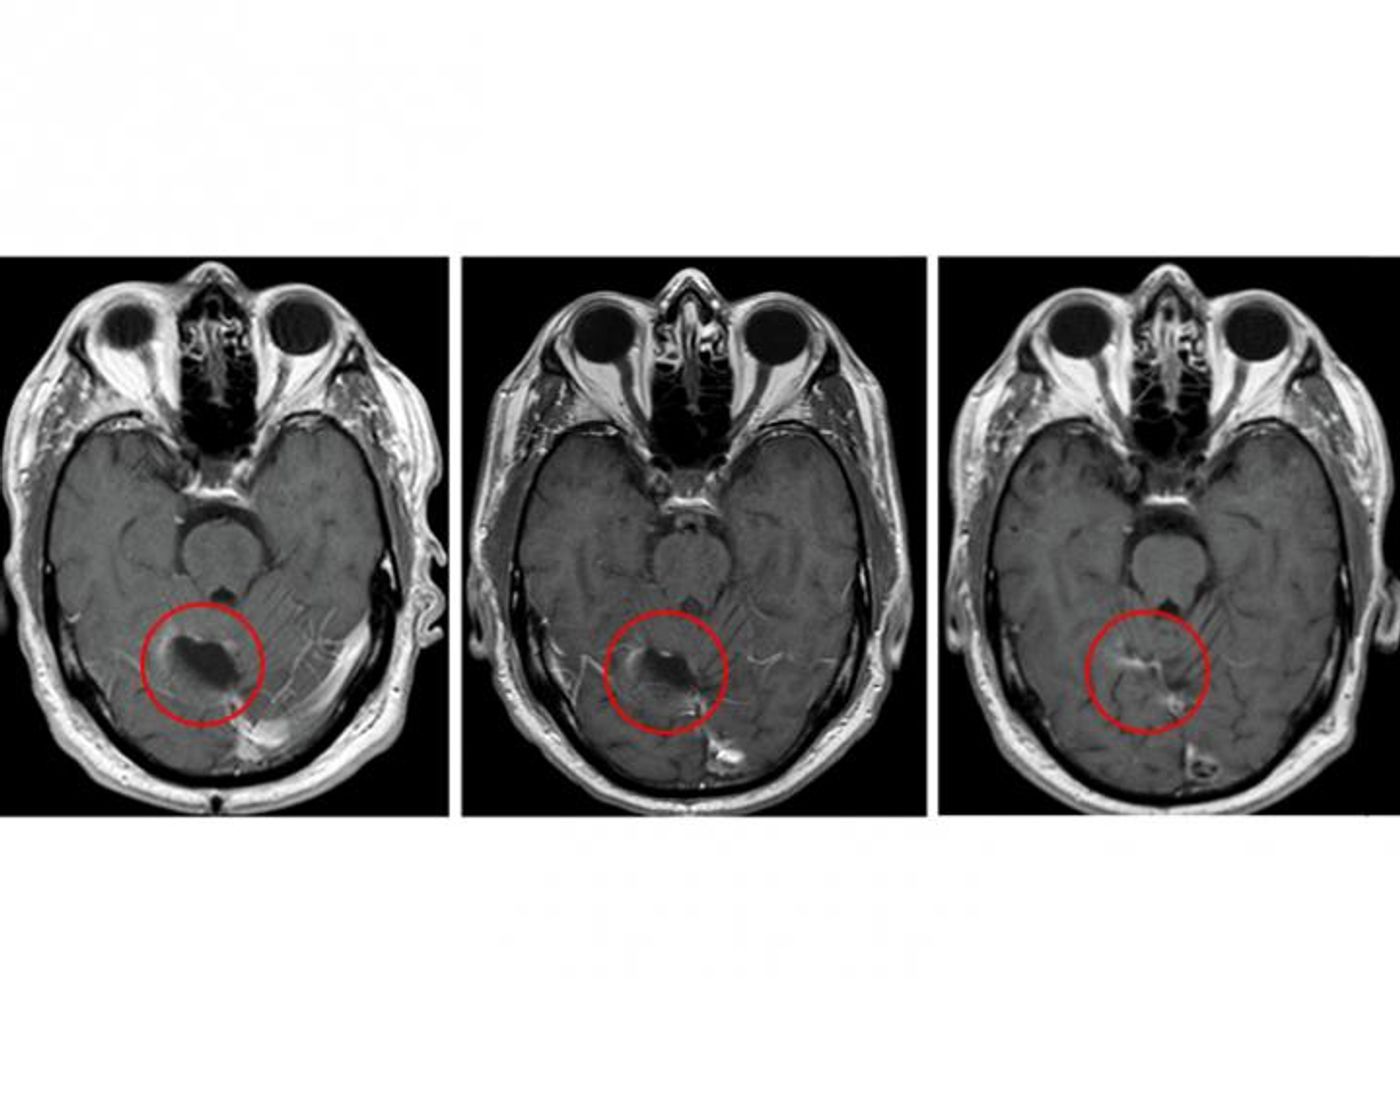

Brain scans from the study's glioblastoma trial.  Credit: Clinical Cancer Research/American Association for Cancer Research

Researchers closely monitored the 11 glioblastoma patients who received the new treatment, and the only side effects seen were expected in connection to temozolomide. Four out of the 11 study participants survived for more than five years following treatment.

"While not a controlled efficacy study, the survival results were surprising, and they suggest the possibility that combining the vaccine with a more intense regimen of this chemotherapy promotes a strong cooperative benefit,” Batich explained.